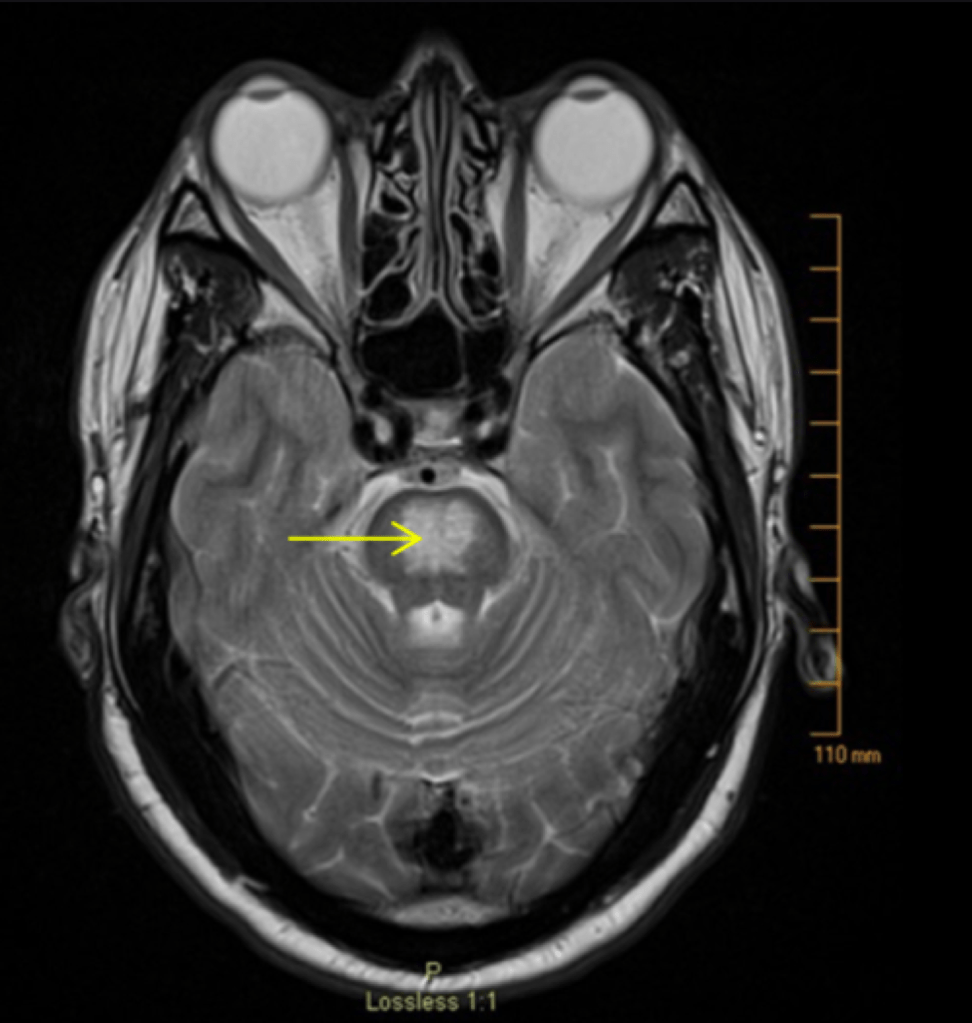

Central Pontine Myelinolysis

Otherwise known as osmotic demyelination syndrome, central pontine myelinolysis is a focal demyelination in pons/extra pontine area leading to neurologic dysfunction. Decrease in serum tonicity causes water to flow across the blood brain barrier, effectively increasing water content of the brain.

The clinical presentation of central pontine myelinolysis is delayed 2-6 days following a rapid elevation in sodium concentration with symptoms such as dysarthria, dysphagia, para/quadraperesis, behavioral disturbances, seizures, confusion, obtundation, coma, with severe cases leading to locked in syndrome.